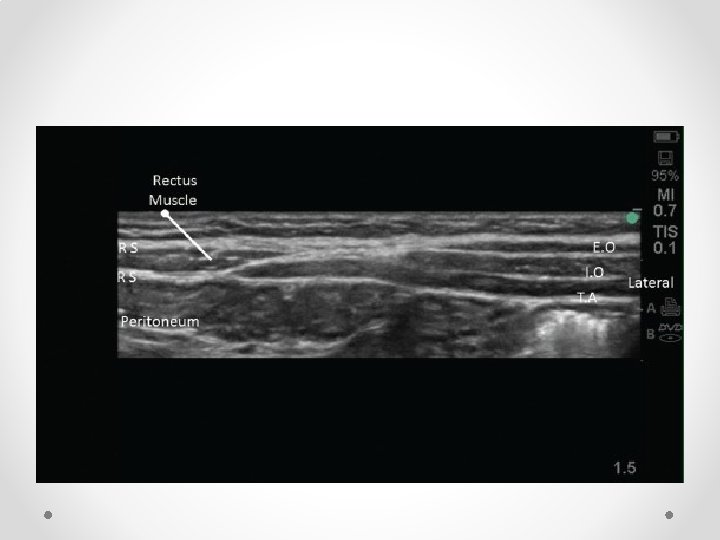

Nerves run between IOM and Transversus abdominus, then posterior to rectus muscle before perforating through it to skin

Above (top) and below arcuate line NB below arcuate line (5 -10 cm below umbilicus) is no fascial sheath deep to rectus abdominus